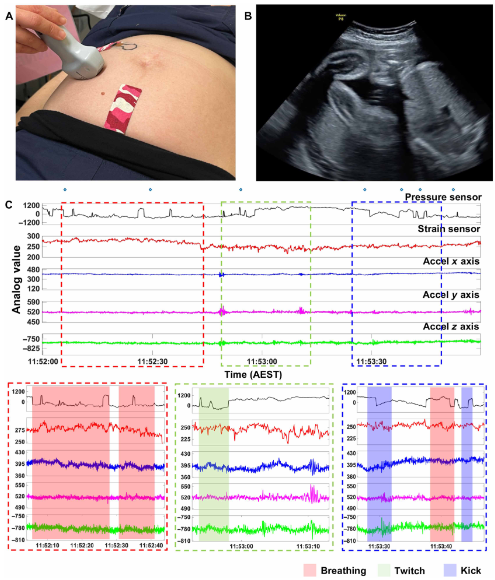

临床研究

本次开发的轻薄“创可贴”式贴片易贴合于孕妇腹部,并在 59 名孕妇半卧位试验中表现良好。压力传感器贴于母体感受到最强胎动的腹部区域,Octa 应变传感器则贴近胎儿肢体方向,同时胸部佩戴加速度计用于记录非胎动数据以去噪。小巧的设计使贴片可与超声同步验证,结果显示压力传感器可精确捕捉局部胎动(如踢动、呼吸、抽搐),Octa 传感器则擅长检测非局部信号(如打嗝、头部动作、胎儿行为状态)。为去除母体动作和环境干扰,本研究利用机器学习算法对胎动进行二分类检测,单传感器系统压力贴片的准确率为 89.5%,Octa 贴片 84.6%,而压力-应变组合系统的准确率提升至 92.2%,敏感性 78.2%,特异性 90.9%,两种传感器互补优势明显。系统对胎动位置变化、体重指数、羊水量及传感器到胎儿的距离均不敏感,在不同温湿度条件下响应稳定,且在连续 25 小时使用及 1000 次循环载荷测试后仍能维持稳定信号,显示了其高环境耐受性和长期可靠性,为连续、精准的日常胎动监测提供了可行方案

多模态信号的记录